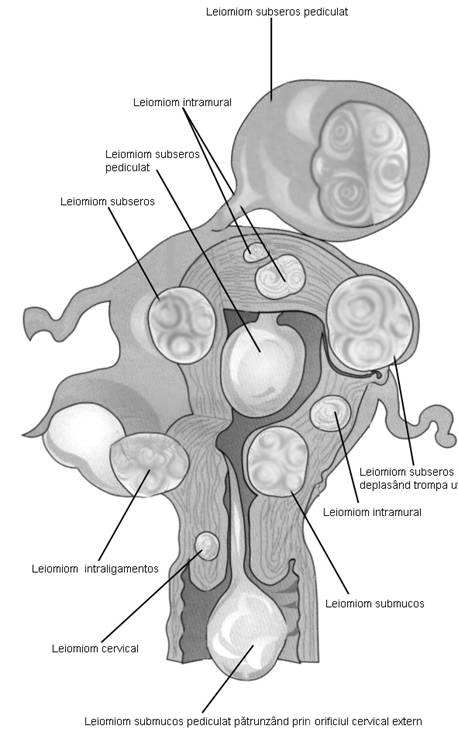

Fibromul uterin - cea mai frecvent intalnita tumora genitala, cu frecventa de 20 - 50% din femei [3].

Aproximativ 90% din fibroame (leiomioame) apar la nivelul corpului uterin. Se descriu, faza miomatozei difuze, fibroame intramurale, subseroase, submucoase, intraligamentare.Mioamele prezinta margini bine delimitate fata de miometru la ecografie, continand arii de mai mare sau mai mica ecogenitate in functie de modificarile degenerative.[1,6]

Fig. Nr.377. Diferite localizari ale fibromului uterin (adaptat dupa Netter